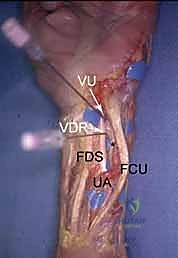

2. The Volar Ulnar Portal (VU)

- Location: Located underneath the ulnar border of the flexor tendons (specifically the flexor carpi ulnaris, FCU, and flexor digitorum sublimis, FDS) at the level of the proximal wrist crease.

- Anatomy: The interval between the FCU and FDS tendons.

- Neurovascular Risks: HIGH. The ulnar nerve and ulnar artery are immediately radial to the FCU tendon. The palmar cutaneous branch of the ulnar nerve is also vulnerable. Extreme caution and meticulous blunt dissection are mandatory.

- Function: Indicated for visualizing and débriding palmar tears of the lunotriquetral ligament (LTIL). It aids in the repair or débridement of dorsally located TFCC tears, especially when triangulation from dorsal portals is difficult. It also assesses the dorsal radioulnar ligament, the ECU subsheath, and the radial TFCC attachment.